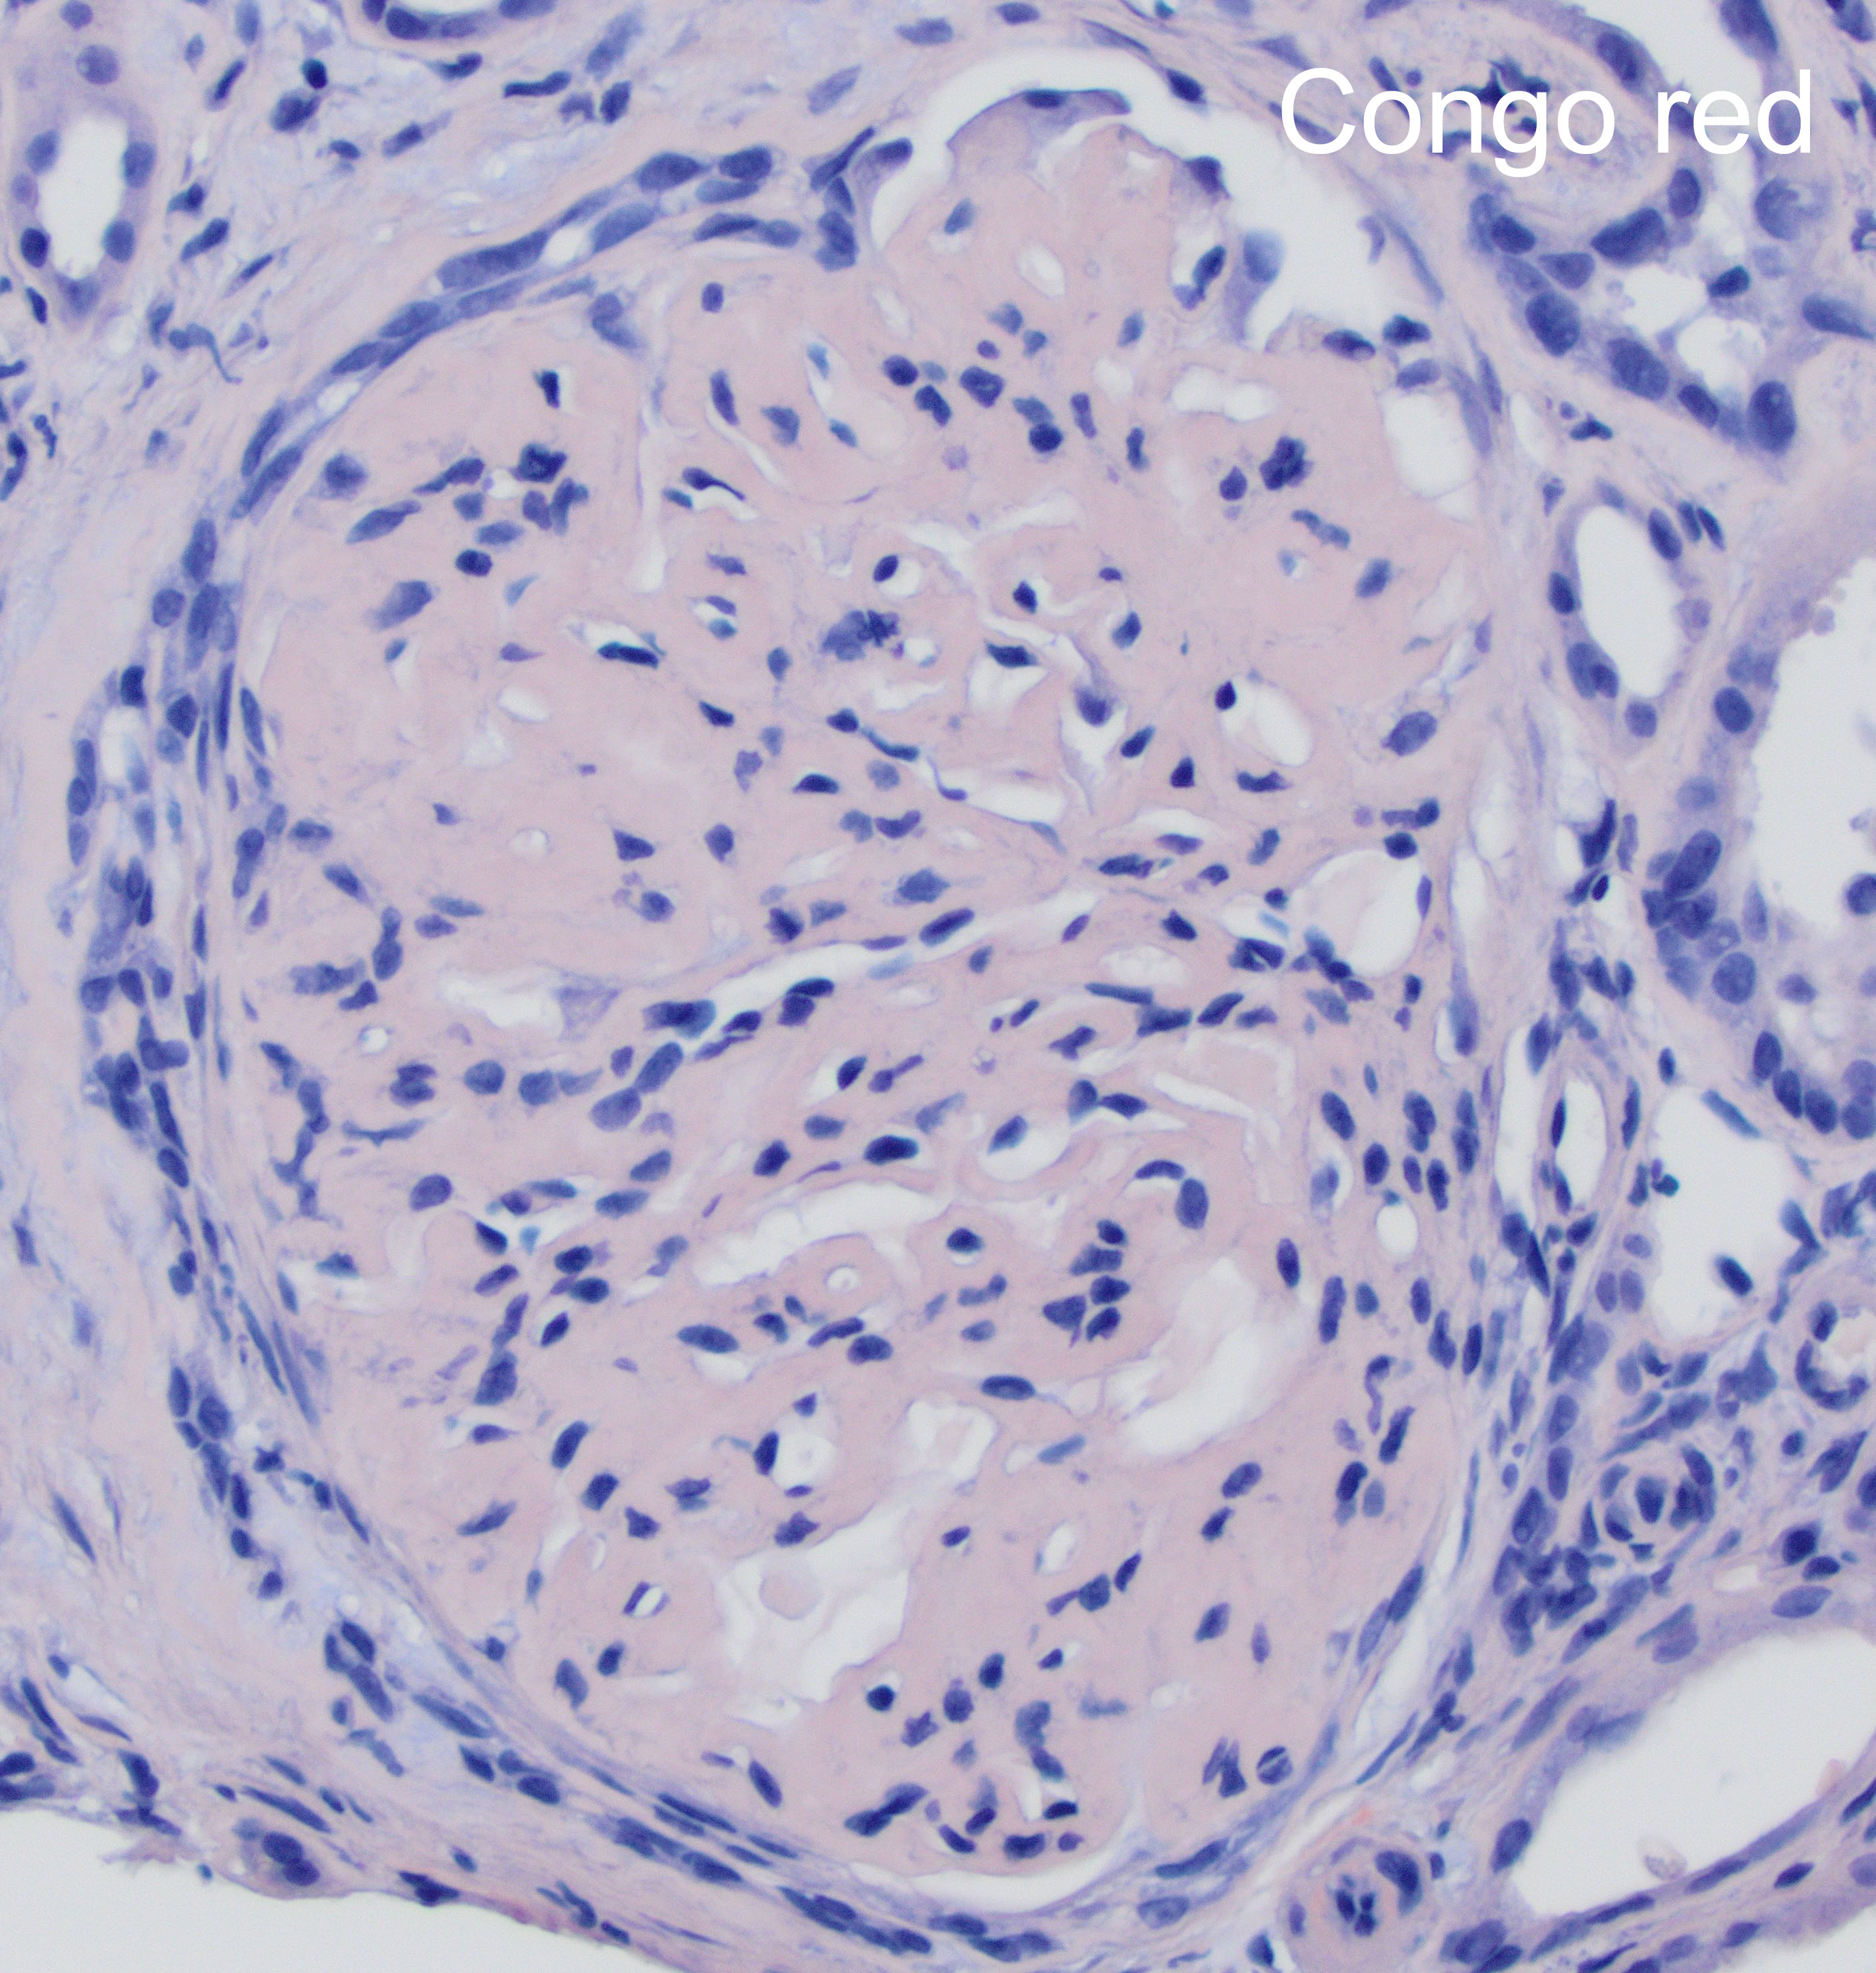

The patient is 32 year-old female with acute kidney injury and nephrotic range proteinuria. A renal biopsy showed diffuse global mesangial and capillary wall expansion by eosinophilic weakly PASH positive material (Silver stain showed in Figure 1), with cellular crescents in 40% and fibrocellular crescents in 5% of the glomeruli. A Congo red stain failed to show apple-green birefringence under polarized light (Figure 2). There was intense immunofluorescence staining with IgG, IgA, C3, and light chains (Figure 3). Electron microscopy showed fibrils with 25 nm average diameter (Figure 4).

FGN is a rare form of glomerulonephritis (less than 1% in native renal biopsies), which diagnosis is historically defined by glomerular deposits of Congo red negative, randomly arranged, straight fibrils without a hollow center that measure between 10-30 nm in diameter (larger than amyloid fibrils) and stain for immunoglobulins. The fibrils are localized in the mesangium and/or along the glomerular basement membrane.

By light microscopy, the most commonly reported patterns of injury are membranoproliferative and mesangial proliferative, with focal crescents in 17-50% of the cases (like in this case which showed less than 50% of glomeruli involved; figure). The deposits result in expansion of the mesangium and/or capillary walls by eosinophilic material that is pale with periodic acid-Schiff, nonargyrophilic, and negative for Congo red. By immunofluorescence, “smudgy” mesangial and/or capillary wall intense staining for IgG (most often IgG4 subclass), usually with C3, kappa and lambda light chains is noted. IgM, IgA and C1q show weaker positive staining in some cases.

The distinction between FGN and amyloidosis is made on the basis of Congo red, DNAJB9 (high sensitivity and specificity for FGN) and composition of fibrils by electron microscopy. Immunohistochemistry against AA amyloid may be used to diagnose a specific type of amyloid deposits. PLA2R (M-type phospholipase-A2 receptor) and THSD7A (thrombospondin type-1 domain-containing 7A) are used in the diagnosis of membranous nephropathy.